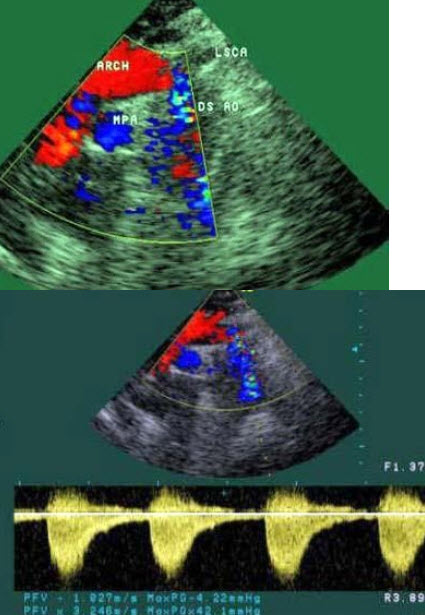

24、单项选择题 动脉导管未闭超声诊断的主要根据是()

A.肺动脉增宽

B.主动脉增宽

C.从降主动脉向肺动脉有收缩期分流血流

D.从降主动脉向肺动脉有双期分流血流;舒张期明显。

E.肺动脉内检出收缩期血流明显大于舒张期血流